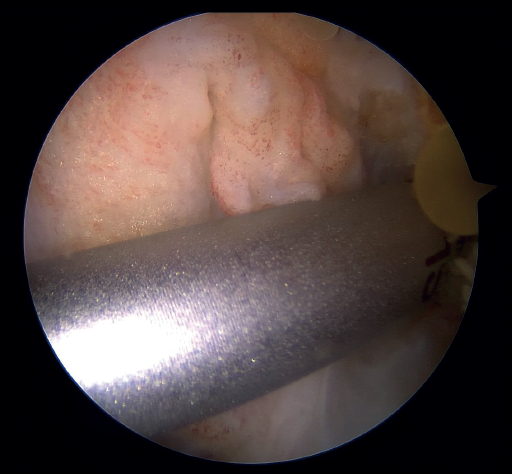

Under arthroscopic vision, it is important to confirm tension of the ACL both in the full range of motion and with the use of a palpator and the Lachman and anterior drawer maneuvers (Figure 6).

As the last step of the procedure, the high strength tape connected to the cortical button is retrieved through the anteromedial portal, where the tibial tunnel retriever thread is located. By loading the tape onto the thread and pulling on it, the tape now lies in front of the repaired ligament and exits through the anteromedial cortex of the tibia, where it is fixed with the knee fully extended with a tenodesis implant (SwiveLock®, HealiCoil®). After completing the procedure, it is advisable to check the tension of the ligament and the InternalBrace®, as well as the absence of impingements and limitations in mobility of the knee (Figure 10).

The ACL possesses healing capacity. The fundamental problem may be the formation of a space between the proximal stump and the wall of the lateral condyle in the insertion footprint. This space, occupied by synovial fluid, may inhibit the formation of an organized hematoma and proper healing of the ligament. The problem may be more mechanical than biological(3). The development of specific techniques such as those described above can improve this situation (Figure 11), but does not guarantee healing or the absence of a separating gap between the extremities that would hinder healing(22).